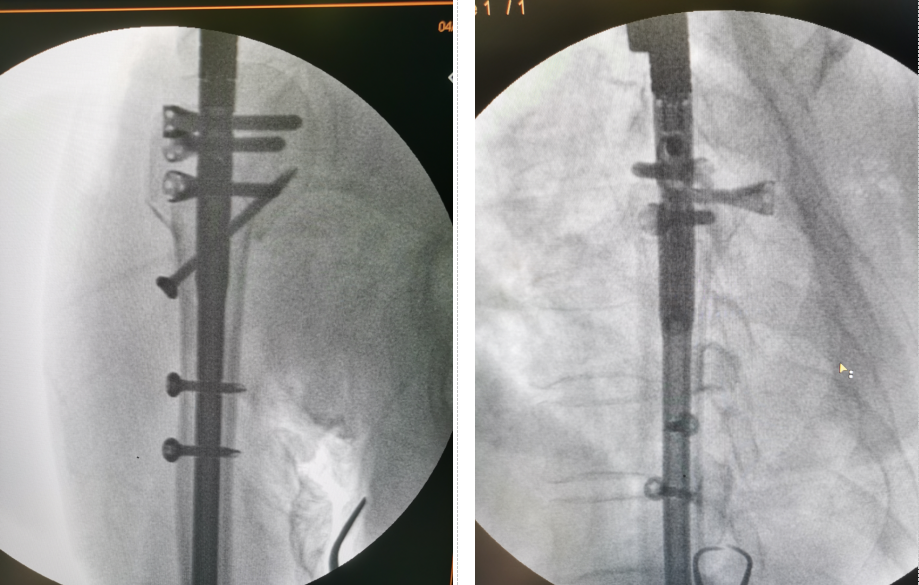

患者,女,73歲,因騎車時摔倒,左上肢著地導(dǎo)致左肱骨近端粉碎性骨折,收住我院骨創(chuàng)外科一病區(qū)。楊猛副主任接診后,給予患者詳細的查體,并完善術(shù)前檢查。左肩關(guān)節(jié)三維CT示患者為較為復(fù)雜的肱骨近端粉碎性骨折,骨折塊移位較大,分型為四部分骨折。出現(xiàn)該類骨折的患者往往骨質(zhì)疏松較為嚴(yán)重,骨質(zhì)量差,骨折粉碎較重,傳統(tǒng)切開復(fù)位接骨板固定為偏心性固定,容易出現(xiàn)內(nèi)固定松動,導(dǎo)致手術(shù)失敗,且切口大、剝離多、出血多。為讓患者以最小的創(chuàng)傷代價獲得最大程度的肩關(guān)節(jié)功能,經(jīng)團隊術(shù)前討論,決定為患者實施目前在國內(nèi)最先進的肱骨近端粉碎性骨折小切口復(fù)位肱骨多維髓內(nèi)釘(Multiloc)內(nèi)固定手術(shù)。

在制定了周密的手術(shù)計劃和康復(fù)計劃后,由楊猛副主任主刀,朱法豪主治醫(yī)師擔(dān)任助手,在麻醉科張顯平副主任醫(yī)師、手術(shù)室張建永護士長的共同配合下,應(yīng)用手術(shù)室先進的X光全透視手術(shù)床,成功完成了手術(shù)。

該微創(chuàng)手術(shù)與傳統(tǒng)術(shù)式相比,手術(shù)時間短,出血少,創(chuàng)傷小,固定方式為多維平面鎖釘中心性固定,更為牢固,患者能夠早期進行肩關(guān)節(jié)功能鍛煉,因此能取得更為滿意的治療效果。